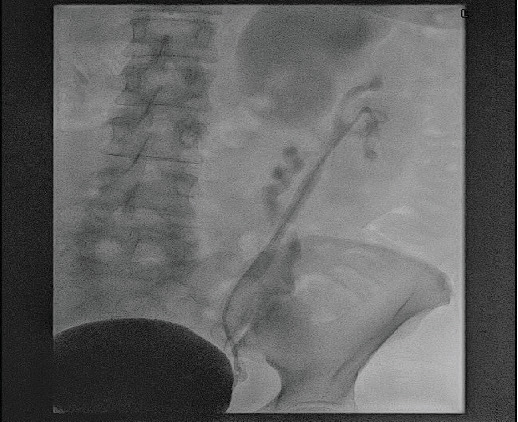

Duplex renal collecting system is a relatively common congenital abnormality affecting equally both pelvicalyceal systems. Although usually it is an incidental finding, it can cause significant problems to the patients such as recurrent urinary tract infections, hydronephrosis, and lithiasis. In this study, we describe an interesting surgical management option for a patient with upper moiety hydronephrosis and lithiasis of the aberrant ureter, achieving resolution of the hydronephrosis and complete removal of the calculus. A 49-year-old female patient presented with symptoms of left colicky pain. During the initial investigation, a left-sided duplex renal collecting system with severely hydronephrotic upper pole moiety and grossly dilated tortuous ureter with distal calculus and ectopic insertion to urinary bladder was identified. On cystoscopy, the upper moiety ureteric opening was identified distally to the urethral sphincter. Under ultrasound guidance, endoscopic transvesical resection was performed distal to the stented lower moiety ureteric orifice, resulting in the identification of the stone and extraction. Short- and long-term follow-up demonstrated no recurrence of the stone and significant resolution of the hydronephrosis. In conclusion, in this case report, we describe an unusual anatomical variation of the upper moiety outflow, and we introduce a new technique of intravesical ultrasound-guided removal of an obstructive calculus.